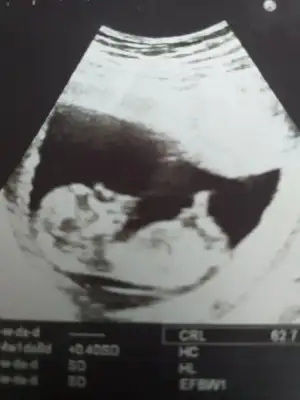

Sanki kız gibi olursa 12 -13 hafta tekrar USG paylasinMerhabalar. Lütfen benim usg lere de bakar misiniz rica etsem?

Ikra meyra 12 hafta oldu doktor söylemedi cinsiyet bir daha gönderim dedim fotomuzu hakkını helal et

12. Hafta ultrasonumuz bize de bakarmisin

Kaç haftalık USG 11 12 13 hafta olmalı sanki kız gibi emin olamadım başka USG de paylasin12. Hafta ultrasonumuz bize de bakarmisin